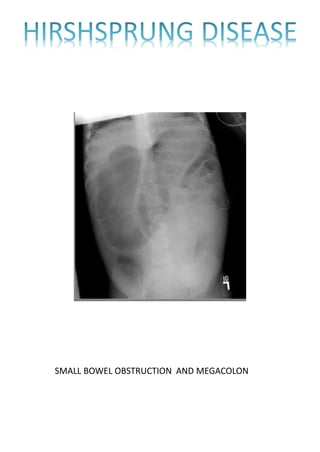

SMALL BOWEL OBSTRUCTION AND MEGACOLON